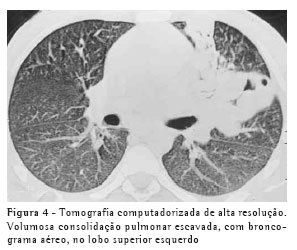

RESULTADOSO achado de imagem mais freqüente, presente nos 7 pacientes, foi consolidação de contornos mal definidos (Figuras 1, 2, 3 e 4), sendo que 5 deles tinham broncograma aéreo de permeio, principalmente na periferia da lesão. Em 3 casos, a consolidação organizava-se sob forma de massa. Em 6 dos 7 pacientes foram observadas, no interior das consolidações, áreas irregulares de escavação, múltiplas em 5 e única em 1 paciente. Em um dos casos não se observou escavação, mas ele mostrava áreas hipodensas de permeio, sugestivas de necrose (Figura 5). Apenas um dos pacientes apresentou nível líquido no interior das cavidades.

A lesão escavada predominou nos lobos superiores, sendo 4 à direita e 1 à esquerda. Em um destes pacientes, ela acometia também o lobo médio. Em 2 casos, ela ocorreu nos lobos inferiores, 1 à direita e 1 à esquerda. Em 4 casos as lesões acometiam apenas os lobos citados, sendo portanto unilaterais. Nos outros 3, atingiam também, em menor intensidade, o pulmão contralateral. Em um caso, havia também escavação de paredes relativamente finas, multisseptada, sem nível líquido, localizada no lobo médio.

Na nossa casuística, o principal padrão de acometimento pulmonar foi o de consolidação com broncograma aéreo de permeio e escavação, presente em 6 pacientes, sendo as escavações múltiplas em 5 casos e única em 1. As consolidações tinham grandes proporções e contornos anfractuosos. Os broncogramas aéreos estavam localizados nas porções periféricas das lesões. O lobo pulmonar mais freqüentemente envolvido foi o lobo superior direito, acometido em 4 pacientes. A maioria dos trabalhos de revisão de casos confirma tais achados.(2,5) Alguns trabalhos relatam que, embora a escavação possa não estar presente no momento do diagnóstico, ela acaba por se desenvolver durante a evolução da doença.(4) Níveis líquidos no interior das escavações foram vistos em apenas um paciente na casuística estudada.